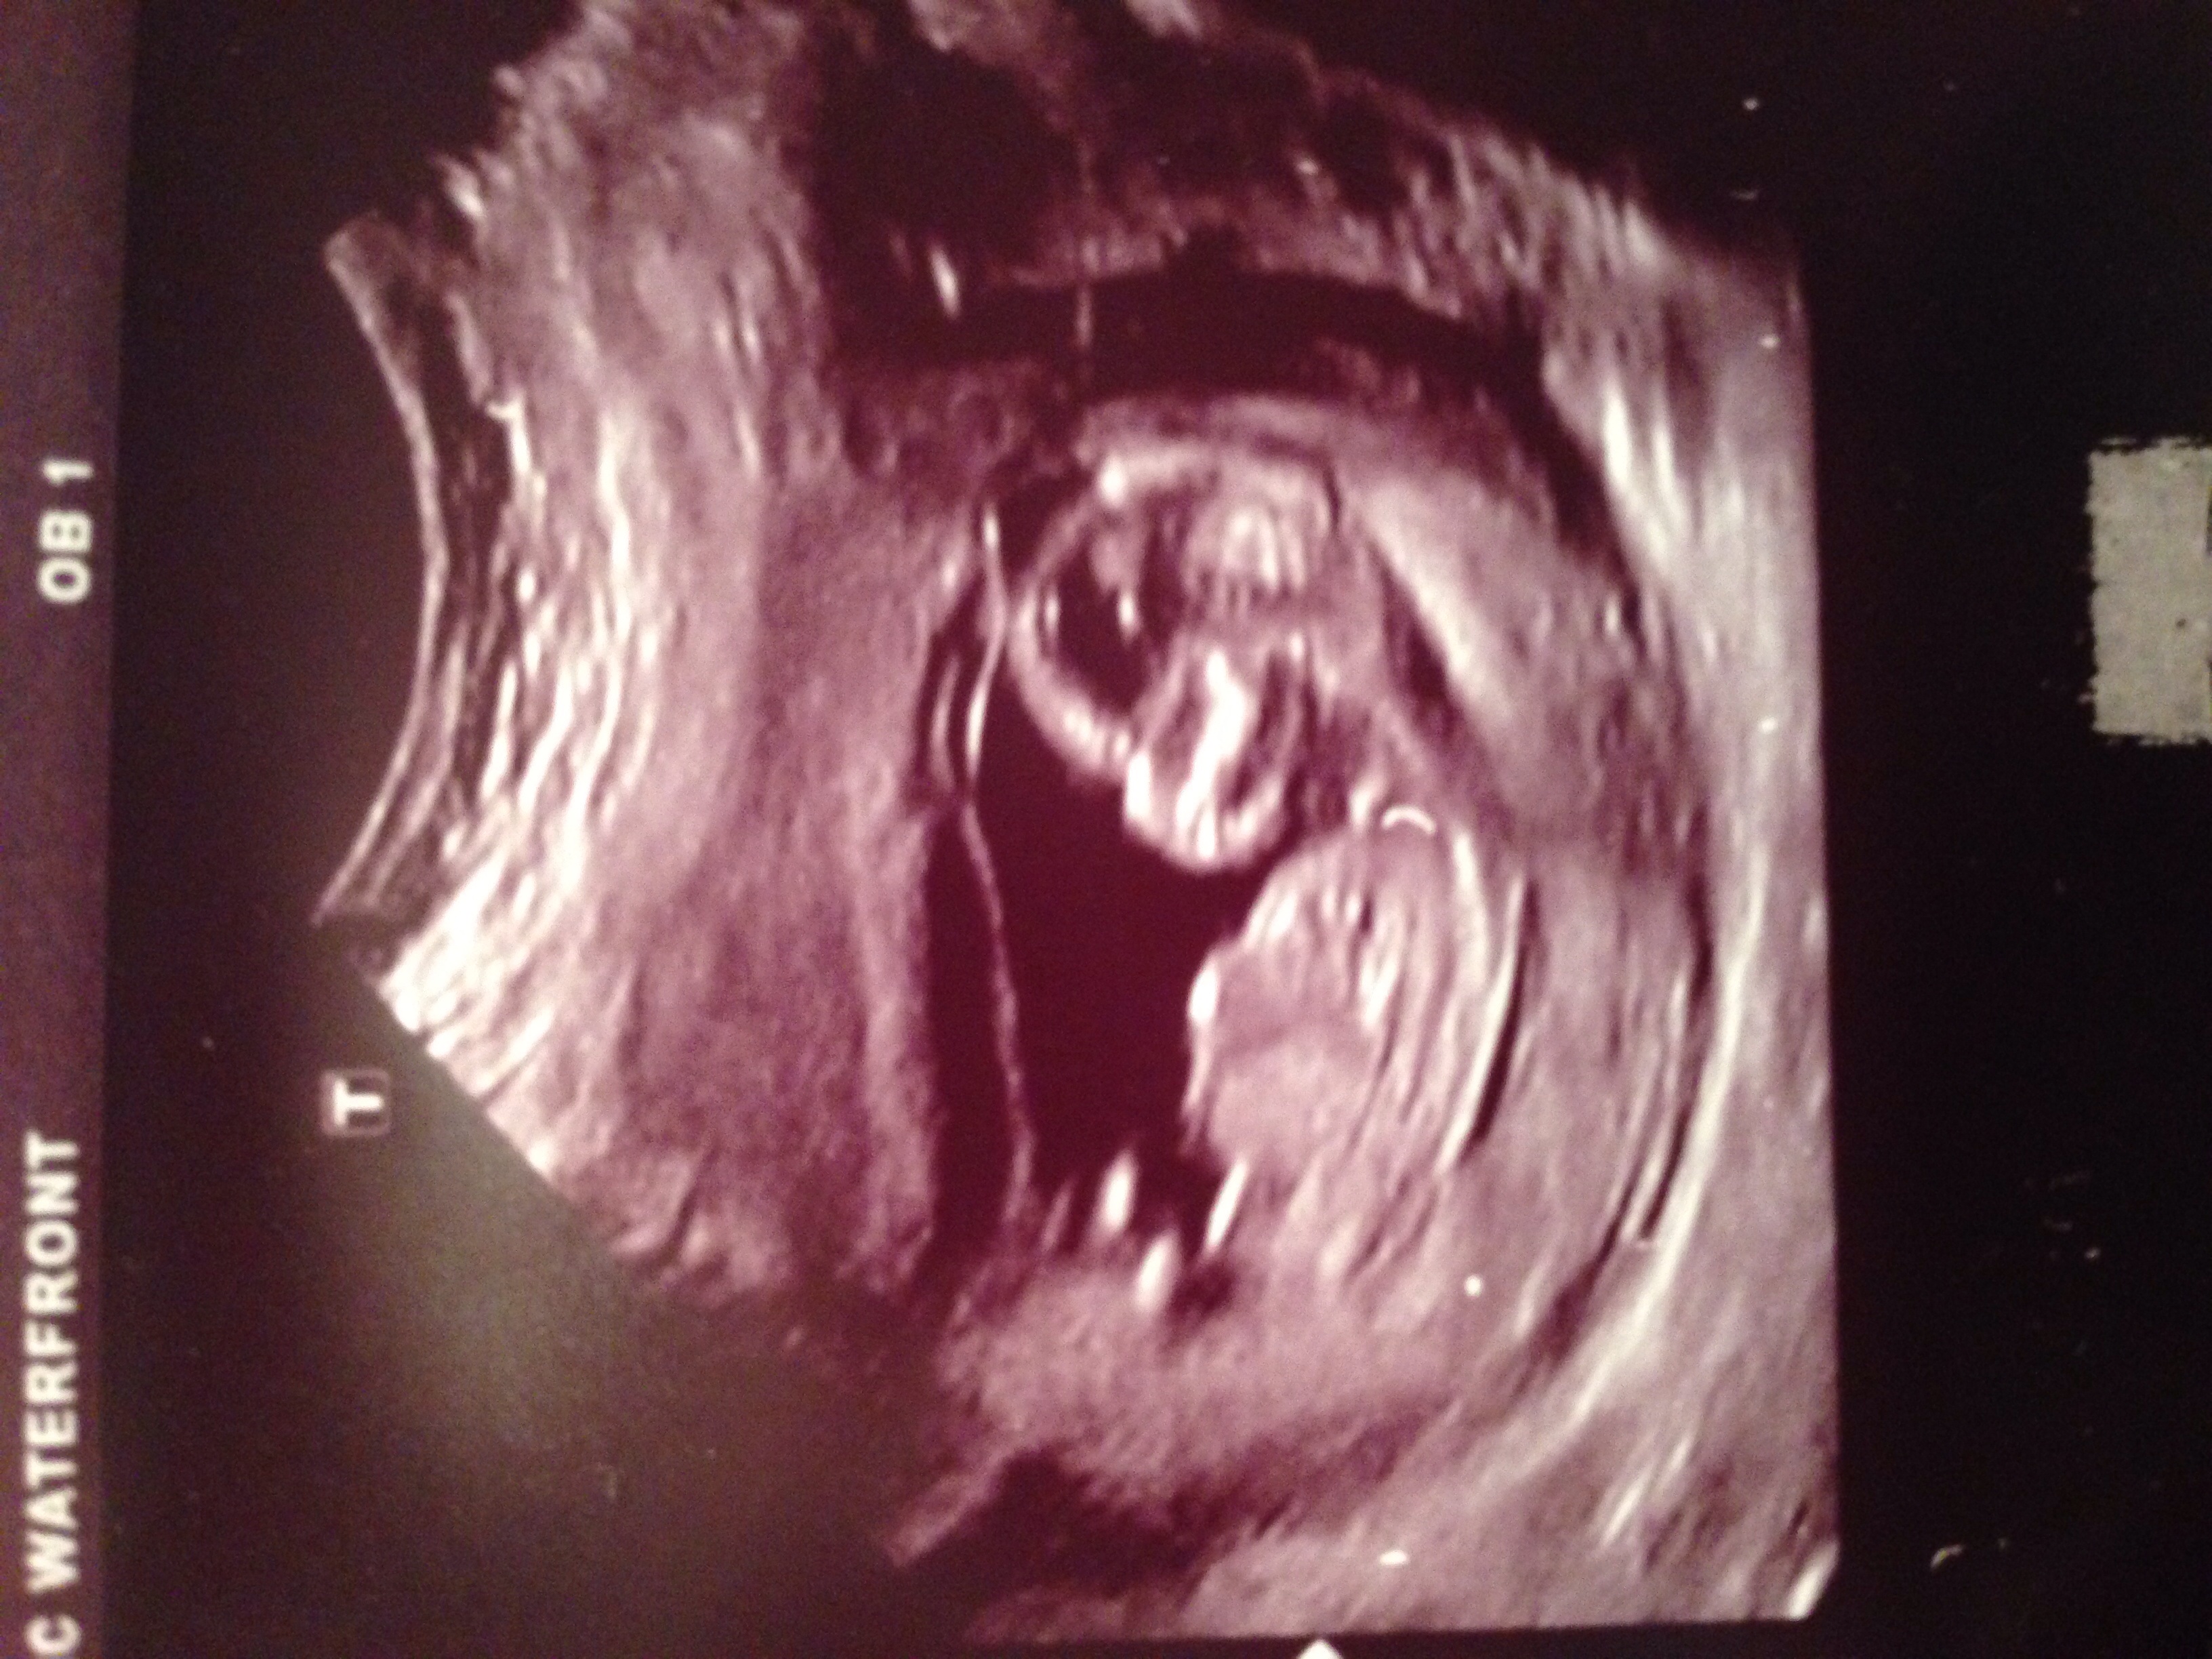

I'm not sure if any of these pictures have any gender clues, but could you please take a look and guess?! Thank you!!

Hmm I think I remember reading that nub shots in the 14th week are not as reliable?

But going by your pics... the first 2 aren't definitive, the 3rd looks very girly and the 4th looks sort of boyish.